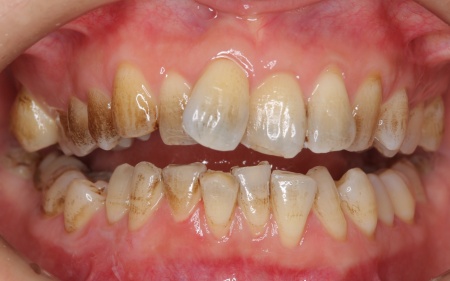

30代女性 デコボコした歯並びをワイヤー矯正とセラミック治療で改善した症例

拝見したところ、歯が全体的にずれたりねじれたりして生えており、歯並びがデコボコしていました。 また、数本の歯にはプラスチックの詰め物が装着されていましたが、経年的な劣化により歯との間に段差が生じています。これも噛み合わせのバランスを崩す原因のひとつになっていると考えられました。 歯並びや噛み合わせの乱れをこのまま放置すると、歯磨きがしにくくなり虫歯や歯周病のリスクが高まるほか、特定の歯に強い力がかかり続けることで将来的に歯の寿命に影響を及ぼすおそれもあります。

治療前